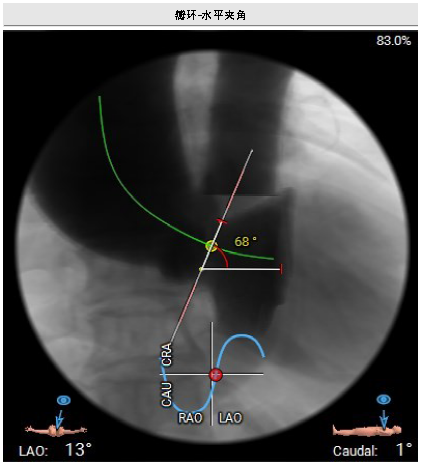

左心评估:左室扩张,室间隔增厚,心尖变薄。瓣环水平夹角68°,提示横位心。

该患者为Type1型二叶瓣,解剖结构异常带来多重挑战:升主动脉明显增宽(最宽处56.3mm)、降主动脉锐折角,增加器械输送阻力;瓣环水平夹角68°,提示“横位心”,加大瓣膜定位难度。手术中,团队特邀北京安贞医院心内科刘新民主任指导,形成针对性方案。